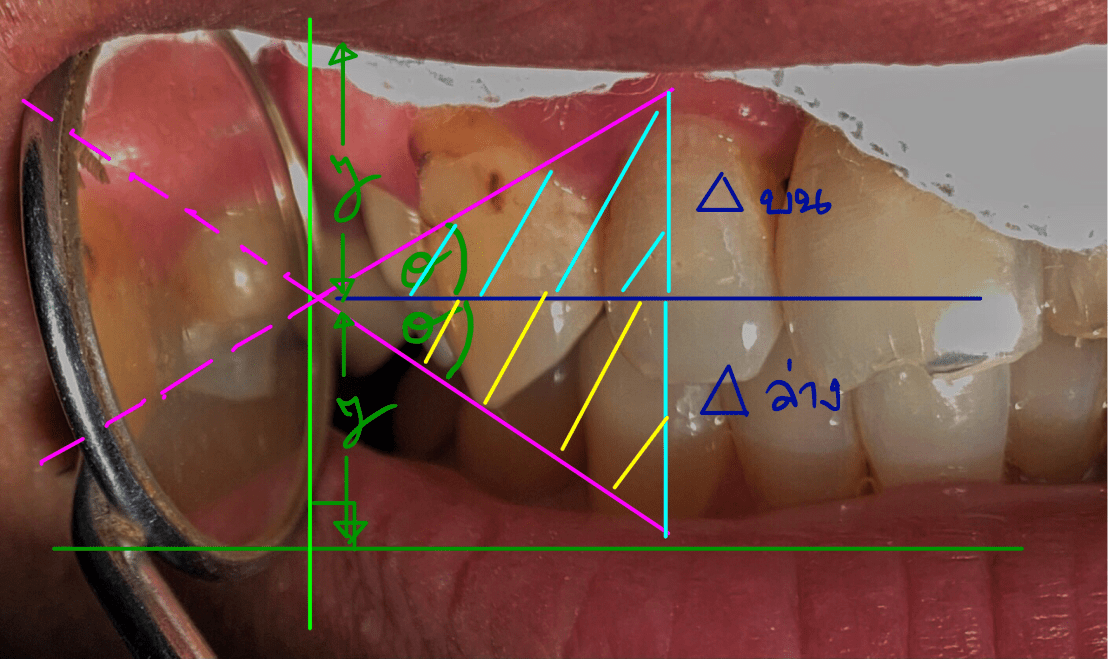

จากคุณสมบัติของสามเหลี่ยมคล้ายที่มุมของสามเหลี่ยม 1 (สีชมพู) และ 2 (สีฟ้า) เท่ากันทั้ง 3 มุม และมีด้านประกอบสามเหลี่ยม เท่ากันอย่างน้อย 1 ด้าน สามเหลี่ยมทั้ง 2 รูป จะมีด้านทุกด้านเท่ากันทุกประการ

ระยะวัตถุ = S = ระยะภาพ = S’

รวมทั้งขนาดวัตถุ (ลูกศรสีเหลือง) ก็เท่ากับ ขนาดภาพ (ลูกศรสีเหลืองหลังกระจกด้วย)

การพิสูจน์ใช้ตรีโกณมิติสามเหลี่ยมคล้าย

รูปสามเหลี่ยมสีชมพู และ สามเหลี่ยมสีเขียว คือ สามเหลี่ยมคล้าย ดังนั้นด้านที่สมมาตรกันจะมีขนาดเป็นสัดส่วนเดียวกัน (เรขาคณิต)

จากรูปสามเหลี่ยมบนและล่างเป็นสามเหลี่ยมคล้าย

ถ้าขนาดของวัตถุ = 2y กระจกต้องมีเส้นผ่าศูนย์กลางอย่างน้อย = y จึงจะมองเห็น cover บริเวณที่ต้องการทั้งหมด